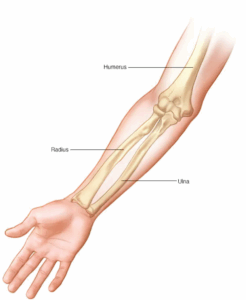

Broken arm (All broken)

A broken arm involves one or more of the three bones in your arm — the ulna, radius and humerus. One of the most common causes of a broken arm is falling onto an outstretched hand.